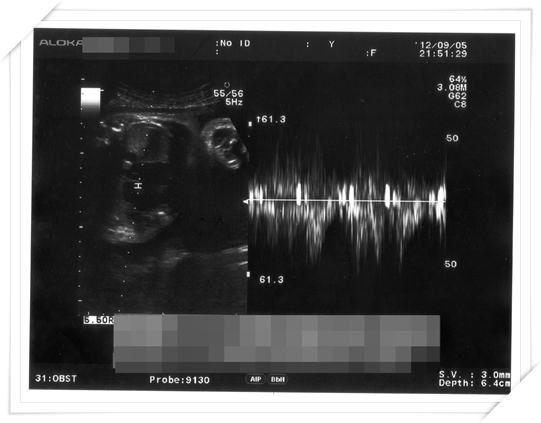

34週的時候我又到了例行產檢的時候啦

產檢的那天其實我還在病懨懨當中 體重當然比之前瘦很多

還好 雖然我瘦了 小鴨還是有照他該長大的速度長大啦~~

只是沒有像之前這麼恐怖 一個月就長一公斤!

反正就是剛剛好就好 醫生也覺得不需要特別 “養胎”

(week 34)